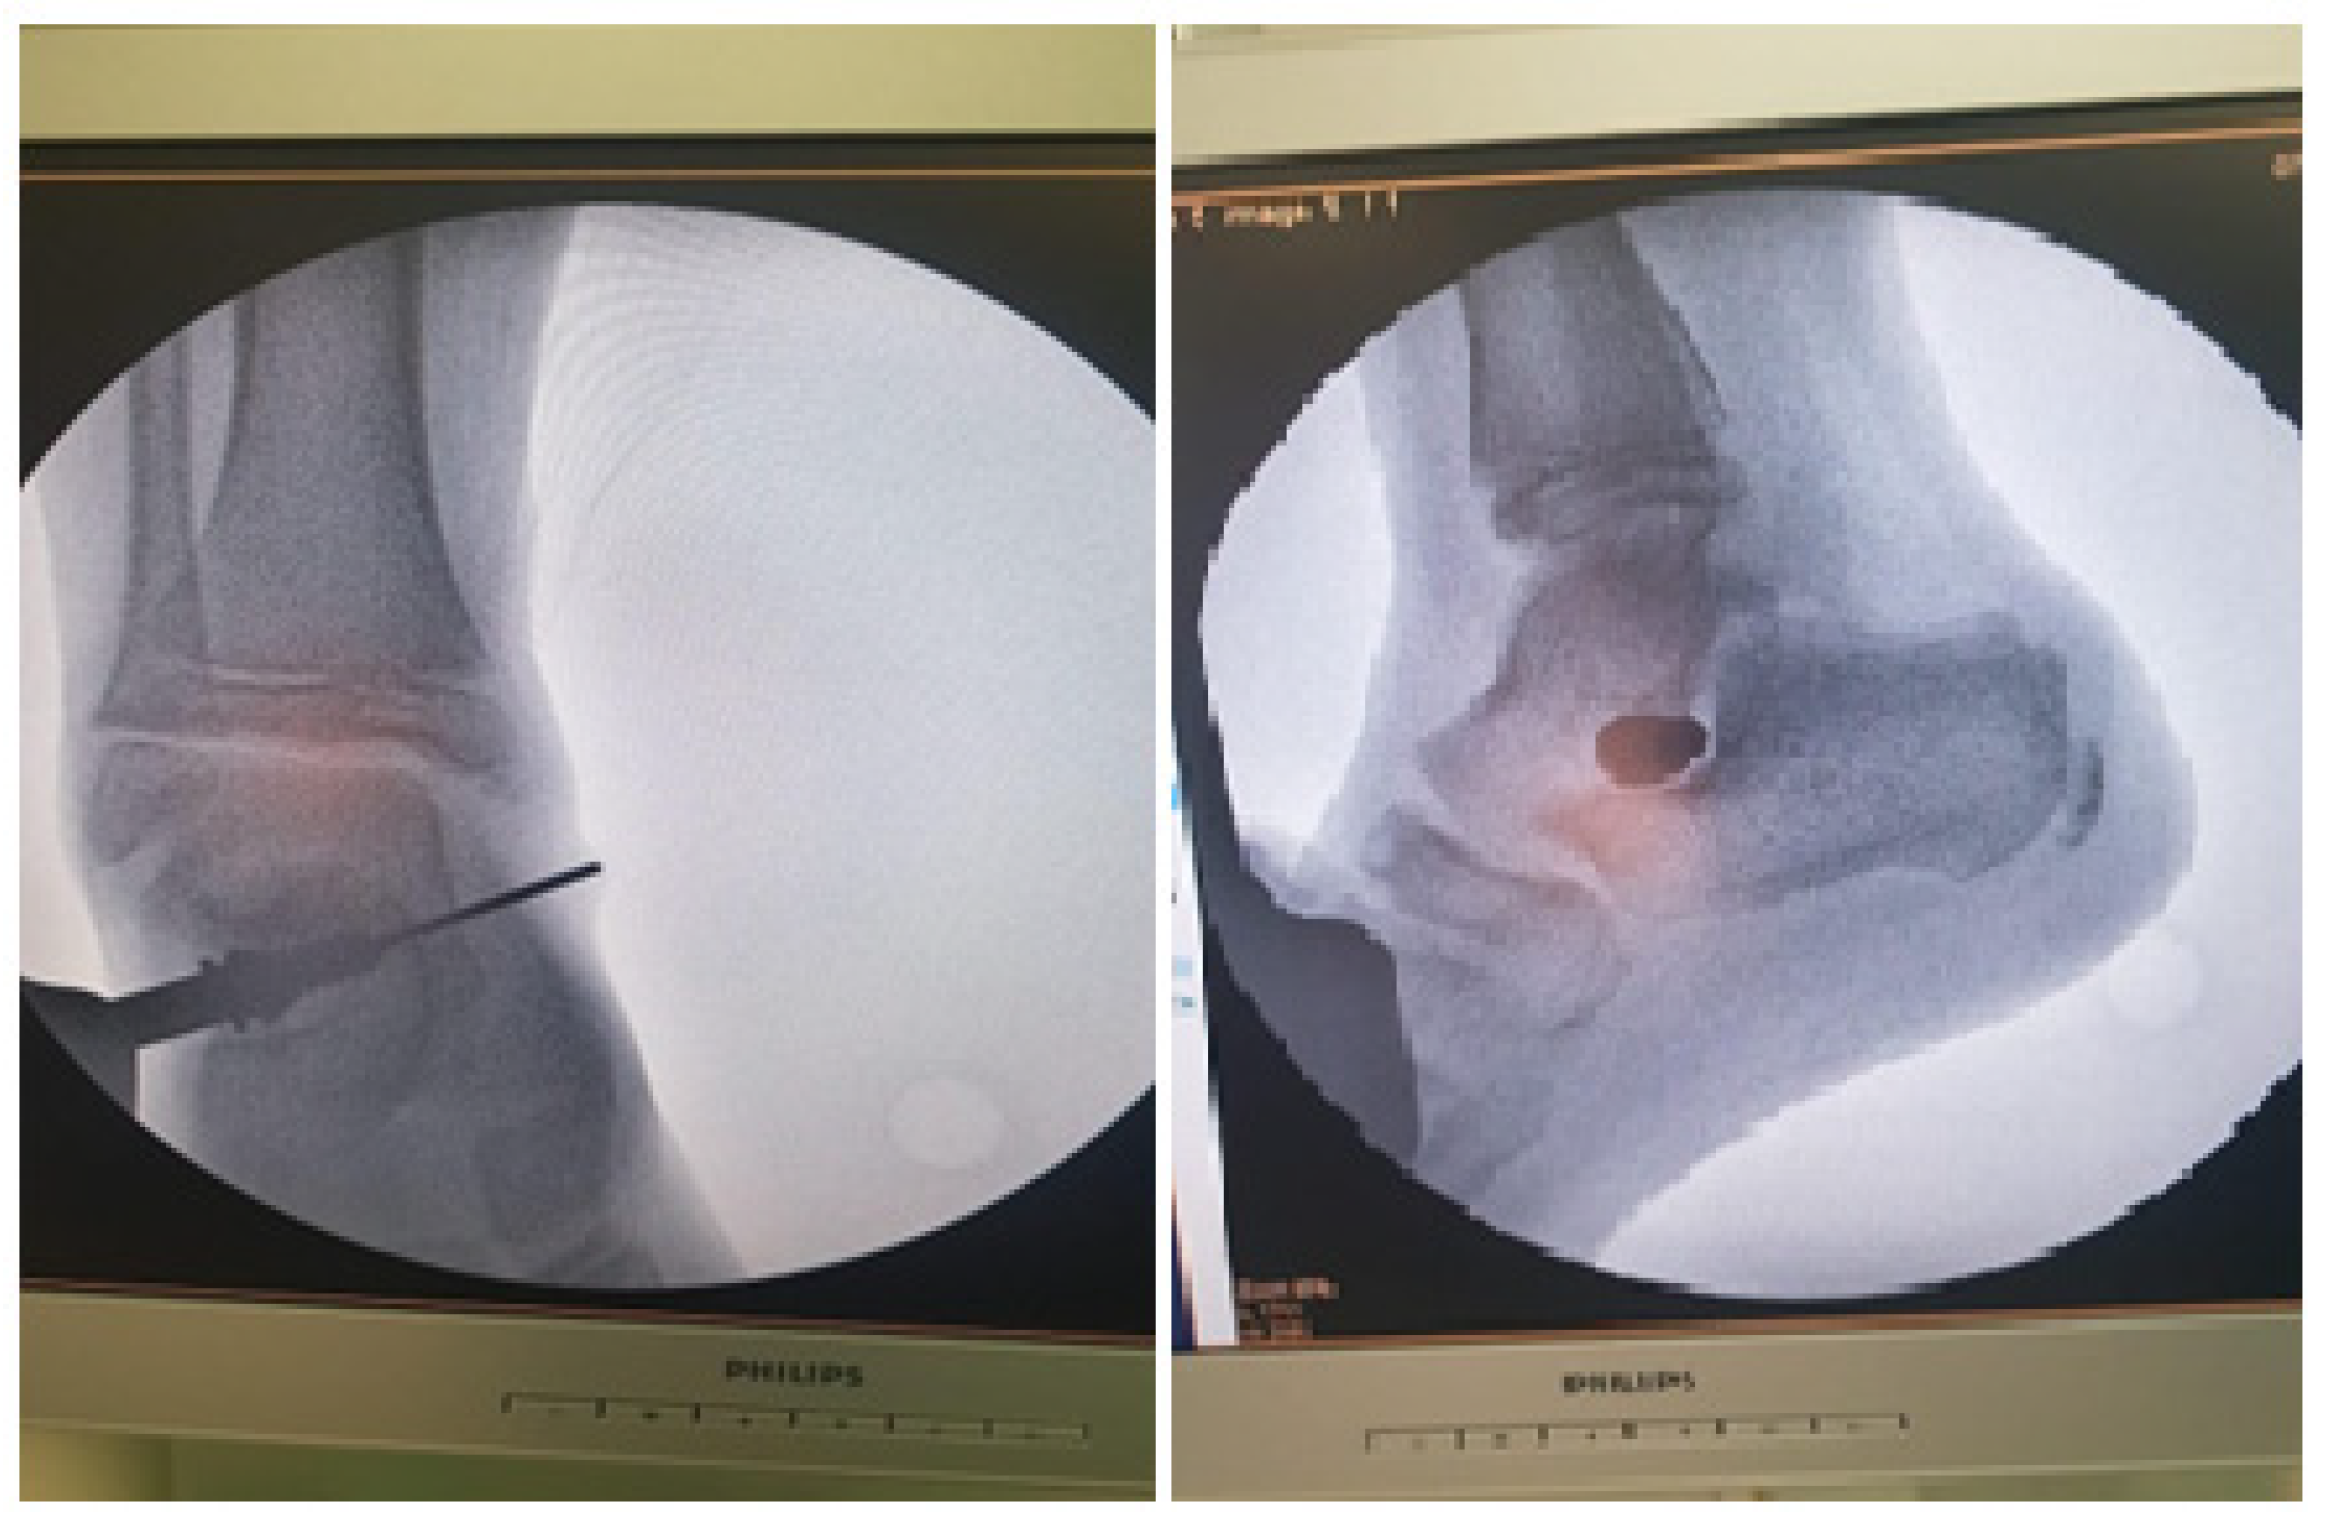

2.4. Surgical Procedure